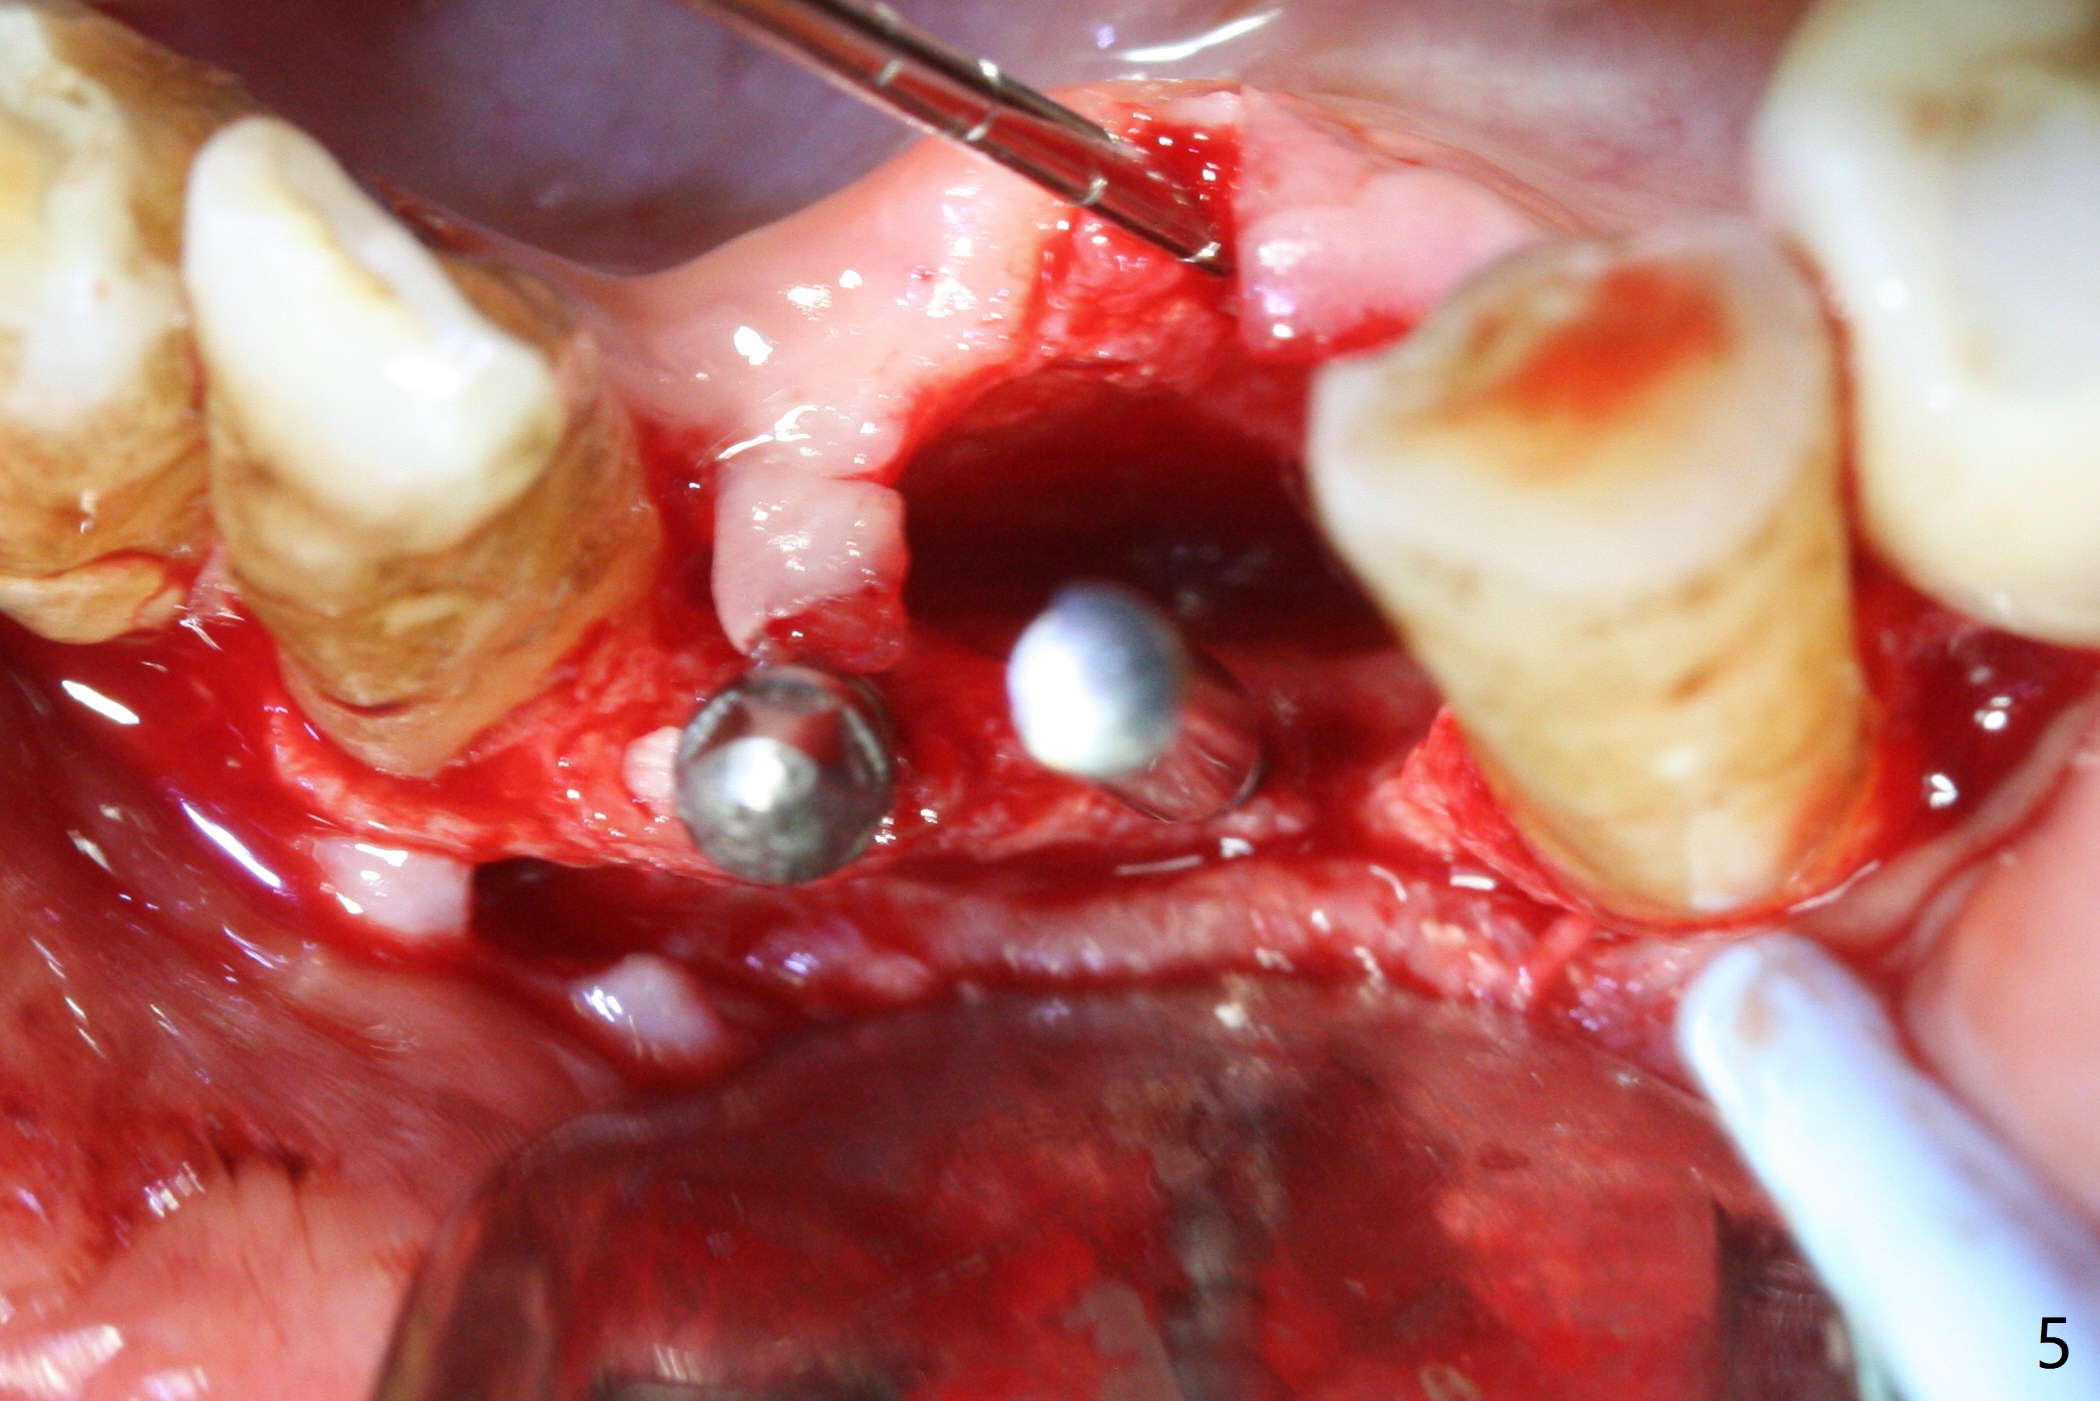

Two and a half months after loss of a 2 mm 1-piece approximately at #23 (Fig.1,2), it appears that the site of #24 (Fig.3 line) is more appropriate because the bone is higher. After removal of the pointed ridge top, osteotomy is initiated with 1.2 mm drill, followed by 1.5 mm one (Fig.4,5). When the 1.5 mm drill is removed, the new osteotomy (Fig.6 *) is mesial to the old one (^). Since the ridge is narrow (Fig.5,6), a 2x14(4) mm 1-piece implant is placed with GBR (Fig.7). Due to overprep, the torque is 20 Ncm. No immediate provisional is fabricated. Instead periodontal dressing is applied around these 2 implants. Two separate provisionals are fabricated when the wound heals. The one at #24 does not stay. The implant at #24 appears to osteointegrate 6.5 months postop (Fig.8). When the crowns are cemented, the margin is supragingival (Fig.9,10). Water Pik is recommended.